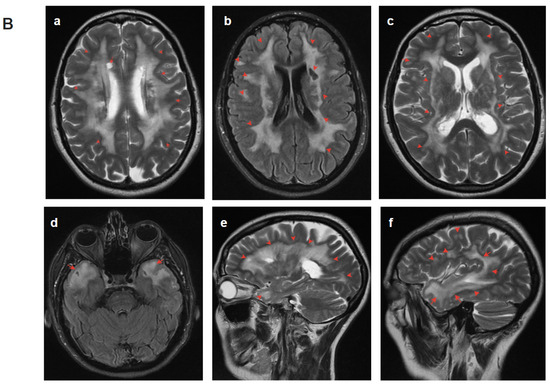

2.4.1. Patient 1

2.4.2. Patient 2

2.4.3. Patient 3

2.4.4. Patient 4.1